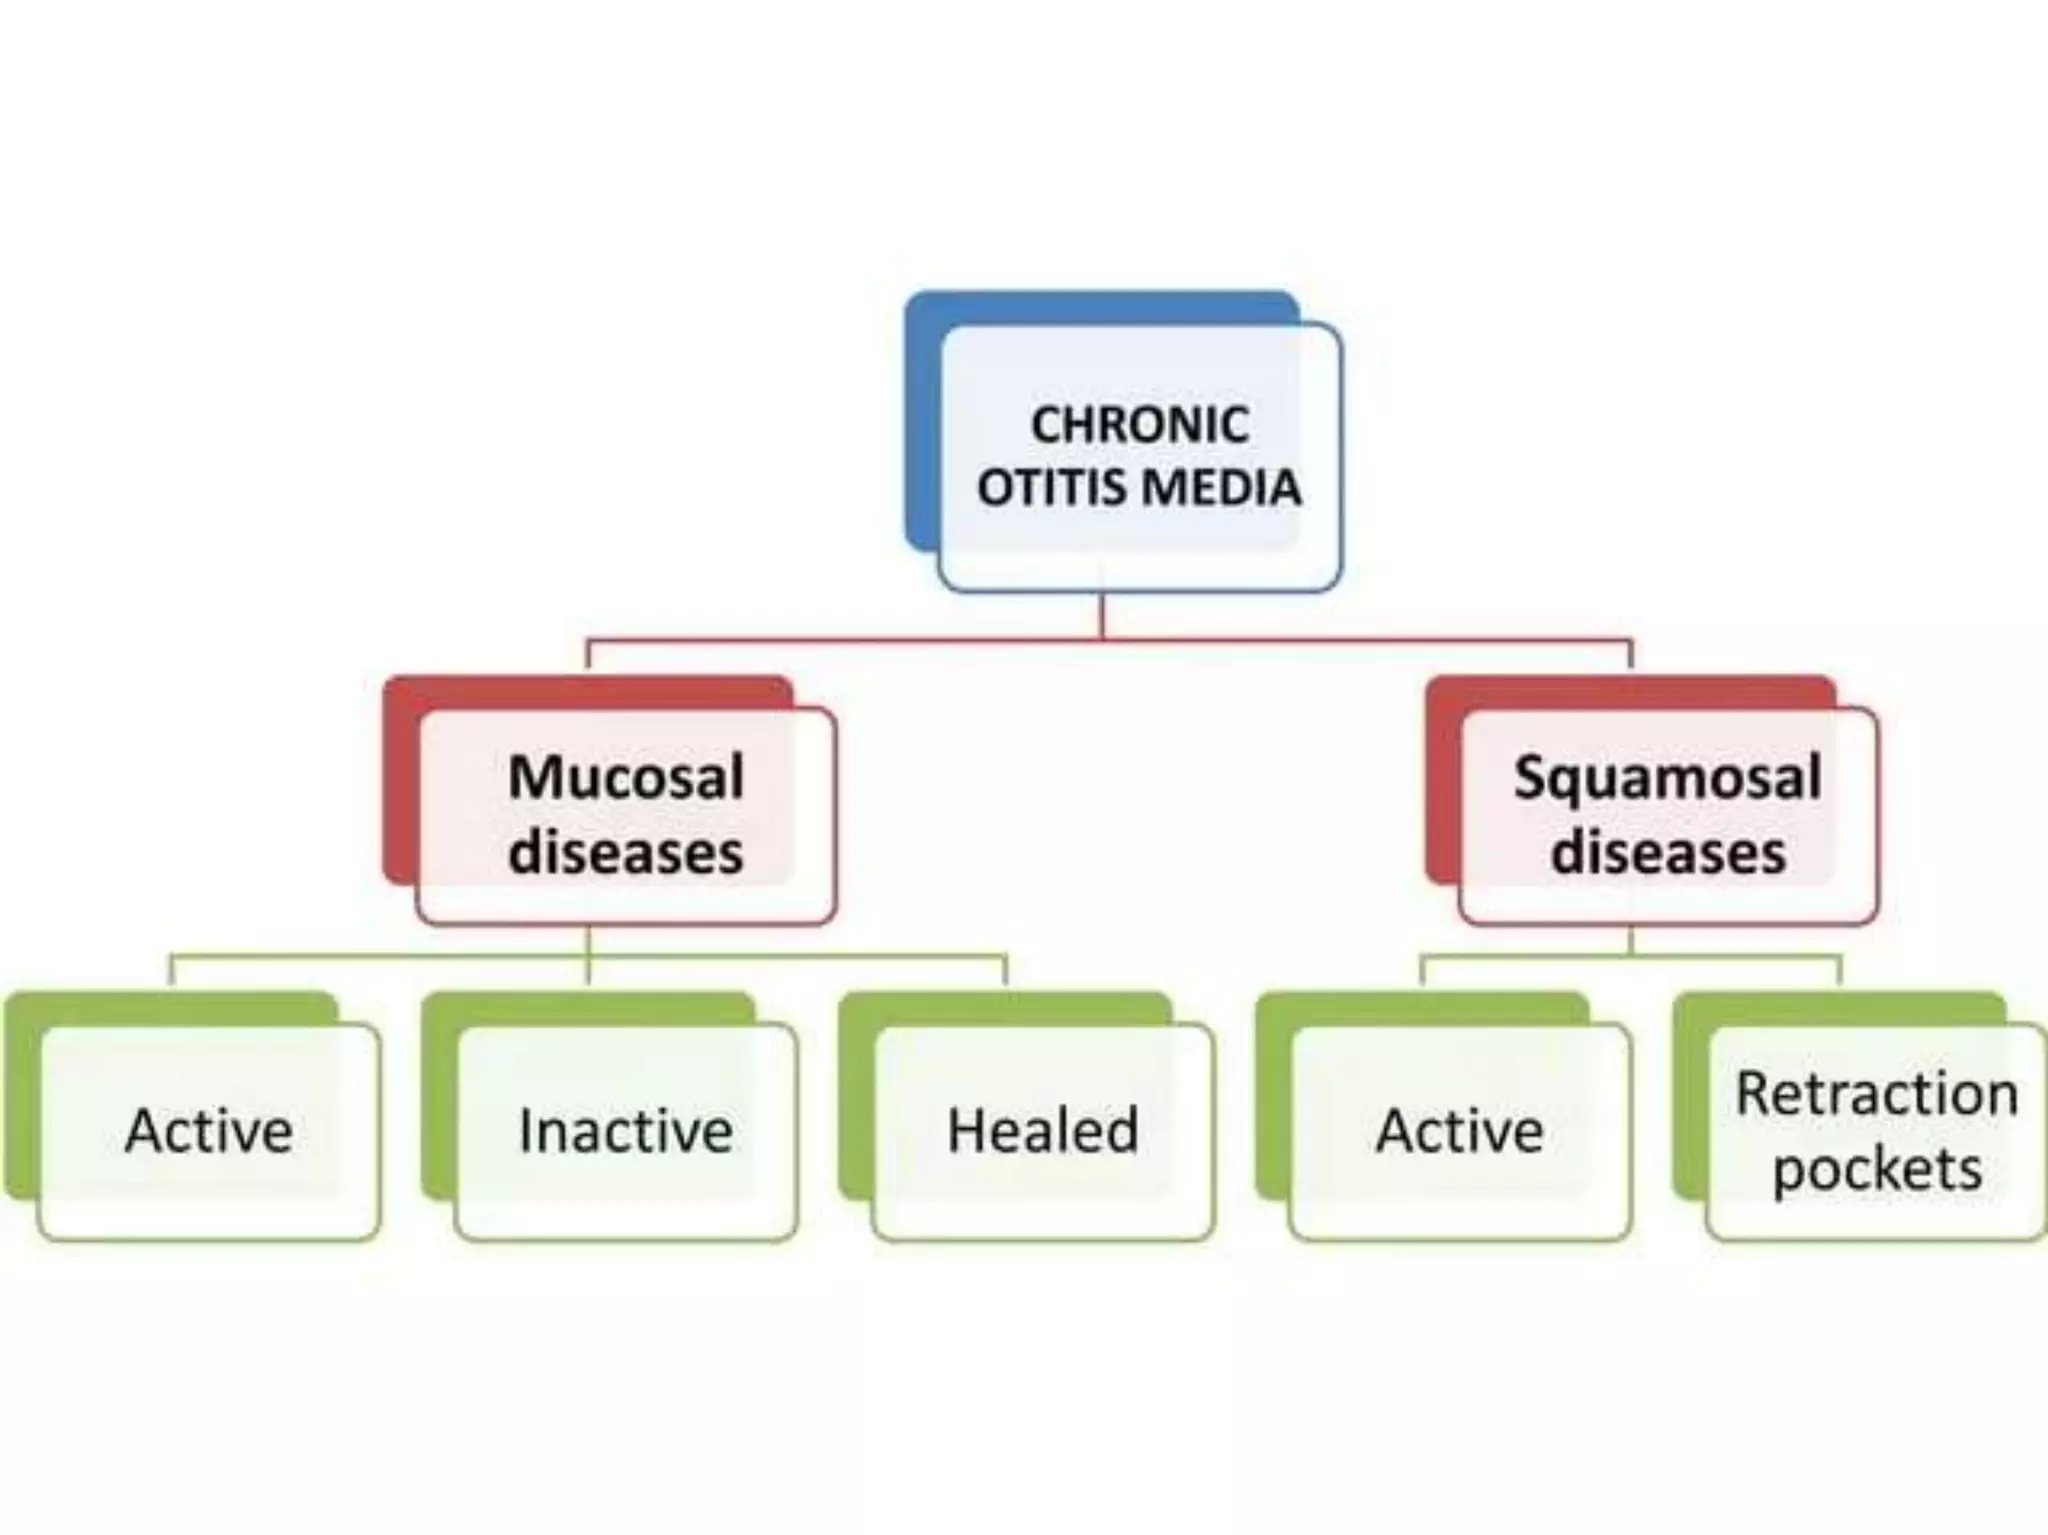

Chronic otitis media is a chronic inflammation of the middle ear and mastoid cavity that presents with recurrent ear discharge through a perforated eardrum. It has several subtypes depending on the state of the eardrum perforation and epithelium. It can be caused by prior acute otitis media, genetics, environment, eustachian tube issues, gastroesophageal reflux disease, craniofacial abnormalities, or immune deficiency.